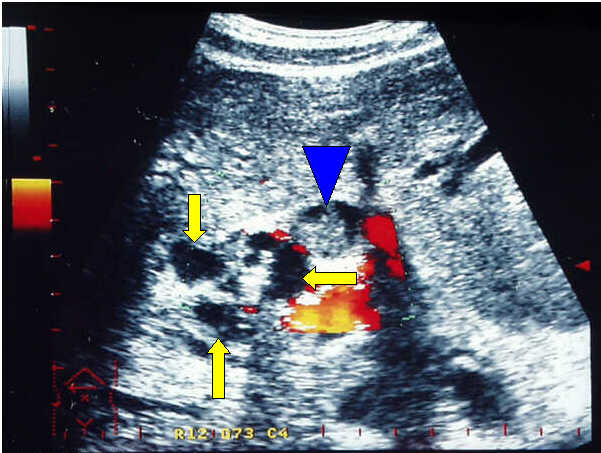

Transverse

Power Doppler scan in a patient with cystic dystrophy of the duodenal wall.

Remarkable thickening of the duodenal wall with presence of little cysts

(yellow arrows); dilated common bile duct with sludge (blue arrow head).